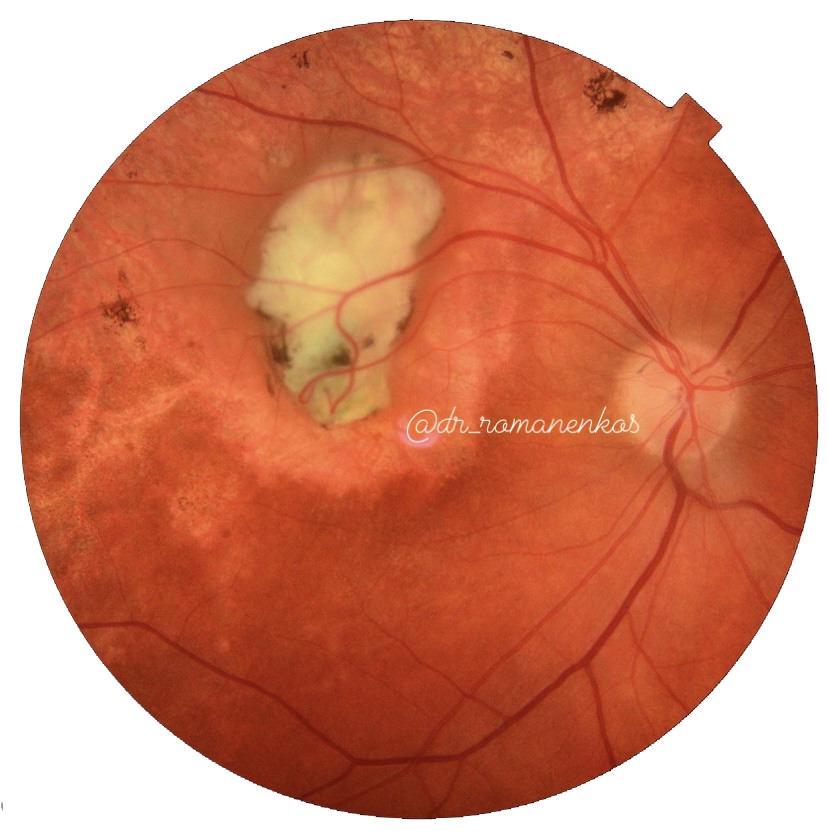

- все материалы (фото фундус камеры, сканы ОКТ взяты из личной практики и разобраны для Вас лично мной) - это ЧЕСТНО! А здесь только так!

- видео, сканы ОКТ с обозначениями, фото глазного с разбором на детали, аудисопровождение, текст и, конечно, ОБУЧАЩИЕ ТЕСТЫ